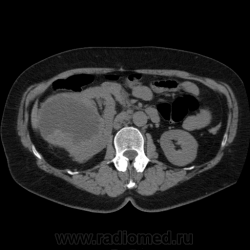

Солитарное кистовидное образование правой почки с неравномерно утолщенными стенками, у узлами в капсуле, накапливающими контраст. Фасция Гарота справа тяжистая. По классификации - киста 4-й категории, крайне велика возможность малигнезации. Может, показалось вовлечение парааортальных лимфоузлов?

В 1986 г. M.A. Bosniak создал “рабочую” классификацию кистовидных образований почек, которая позволяет предположить доброкачественность или злокачественность кистозных образований при распределении их по радиологическим критериям на 4 основные категории. Образования I и II категорий являются заведомо доброкачественными и поэтому нуждаются в динамическом наблюдении или, по показаниям, в лечебной пункции со склеротерапией под контролем УЗИ или КТ. Образования III категории могут быть как доброкачественными, так и злокачественными, а образования IV категории – кистозные почечноклеточные раки.

Третья категория – более сложные кистовидные образования, которые демонстрируют какие-либо радиологические признаки злокачественности. Некоторые из этих образований оказываются доброкачественными (например, сложные кисты, мультилокулярная кистозная нефрома, геморрагические кисты), другие злокачественными (почечные кистозно-клеточные карциномы). Одним из критериев, которые заставляютотнести кистовидное образование почки к III категории, является повышение плотности ее стенки. При КТ у кистовидного образования выявляется плотная (вплоть до обызвествления) стенка по всему периметру кисты, хотя образование может сохранять некоторые признаки простой кисты почки. Следующим критерием является характер отложения кальцинатов. Если при КТ в образовании определяется большое количество кальцинатов, расположенных глыбками (как на периферии образования, так и в центре), если из-за этого стенки и перегородки становятся утолщенными, неправильной формы, то данное образование следует отнести к III категории. Наличие множественных перегородок толщиной более 1 мм, видимых утолщений в месте прикрепления перегородок к стенкам кисты позволяет также отнести данное образование к третьей категории. Большое количество тонких перегородок в образовании определяет его как сложную кисту. Такие образования крайне сложно дифференцировать как доброкачественные или злокачественные, но они чаще по КТ-картине выглядят как злокачественные. При КТ определяется негомогенное многокамерное образование округлой или неправильной округлой формы, возможно с капсулой. Плотность образования неоднородная, пониженная относительно паренхимы, в полости образования видно большое количество перегородок.

IV категория – поражения явно злокачественные, обычно кистозные почечно-клеточные карциномы. Основными симптомами кистозной опухоли при КТ являются: неправильная форма кисты, негомогенность структуры образования с участками некроза, деформация почки, нечеткая граница между кистой и паренхимой почки, плотностные показатели могут быть выше, чем в кистах (+20…+40 Н), т.е. близкие к плотности почечной паренхимы. Капсула имеет неравномерную толщину, часто обызвествлена по периферии. Возможна визуализация дополнительных фокусов образования (кажущееся увеличение образования в размерах и изменение его конфигурации) после введения контрастного вещества. Но самым важным симптомом является увеличение плотности внутреннего содержимого после внутривенного введения контрастного вещества. Часто на серии срезов удается выявить эндофитные гребневидные фестончатые разрастания, выступающие в просвет кистозной полости. Особенно хорошо этот мягкотканый васкуляризированный компонент опухоли проявляется при внутривенном контрастировании

Всё верно, я тоже пользуюсь данной классификацией по Босняку, кистозно-солидное образование правой почки я отнёс к 4 категории, нужно отметить, что преобладает кистозный компонент, но солидный компонент довольно приличный и значительно накапливает контрастное вещество до 80-90HU, четко капсулу образования не отграничить. Ко всему этому в паренхиматозную фазу четко дифференцируются единичные парааортальные и паракавалльные л/узлы. С большей степенью вероятности в данном случае cr почки. Пациентка на следующей неделе будет госпитализирована для верификации.

Описание изменений, выявленных при микроскопическом исследовании: опухоль представлена крупными альвеолярными структурами из светлых, оптически пустых клеток с мелкими гиперхромными ядрами, опухоль частично инфильтрирует капсулу почки, полностью прорастает стенку почечной лоханки, образуя полиповидные структуры. Одиночные опухолевые эмболы в сосудах почки. Отдельно присланный узел представлен тканью почки с опухолевым узлом, строение которого соответствует выше описанной опухоли. В воротах почки патологических образований не найдено. Во всех исследованных лимфоузлах (6 шт.) метастазы опухоли с замещением всей ткани лимфоузлов.

Патоморфологическое заключение: массивный светлоклеточный почечно-клеточный рак почки с частичной инфильтрацией капсулы, прорастанием в ЧЛС, опухолевыми эмболами в сосудах, множественными метастазами в забрюшинные лимфоузлы (6 шт